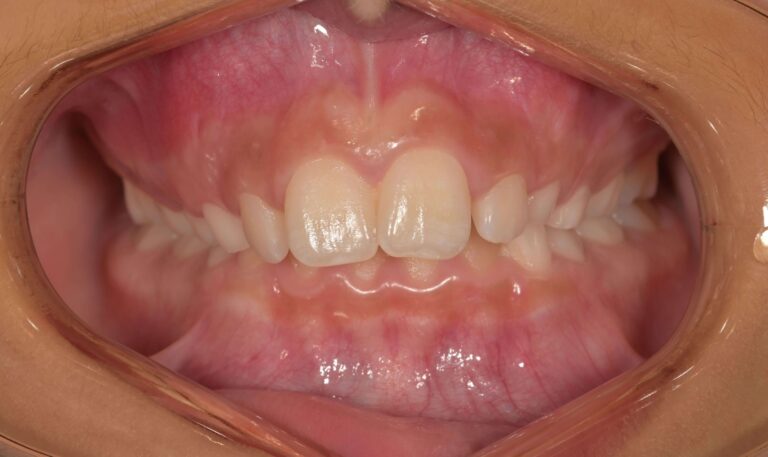

Дълбока захапка

Дълбоката захапка е най-често срещан проблем, при който горните предни зъби покриват вертикално долните зъби. В някои по-тежки случаи горните зъби могат да стигат до долните венци или долните зъби да опират в небцето. Дълбоката захапка най-често се проявява при вредни детски навици, ранна загуба на млечни зъби и несъответствия в растежа на челюстта.

Усложнения, които могат да настъпят – Ако не се лекува, дълбоката захапка причинява прекомерно износване на зъбите, повишена чувствителност, заболявания на венците и болка в челюстта.